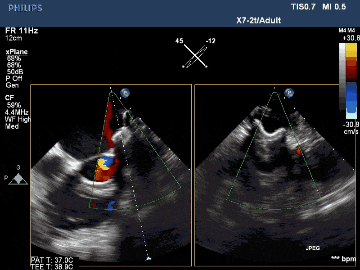

術后TEE影像示封堵完全